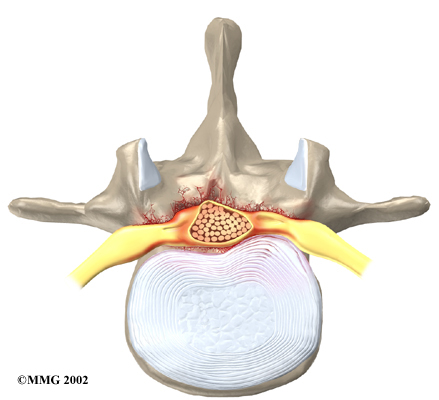

The back portion of the spinal column forms a . When the vertebrae are stacked on top of each other, these bony rings create a hollow tube. This bony tube, called the spinal canal, surrounds the as it passes through the spine. Just as the skull protects the brain, the bones of the spinal column protect the spinal cord.

Degeneration: Degeneration is the most common cause of spinal stenosis. Wear and tear on the spine from aging and from repeated stresses and strains can cause many problems in the lumbar spine. The intervertebral disc can begin to collapse, and the space between each vertebrae shrinks. Bone spurs may form that stick into the spinal canal and available to the spinal nerves. The ligaments that hold the vertebrae together may thicken and also push into the spinal canal. All of these conditions cause the spinal canal to narrow.

Disc herniation: Spinal stenosis can occur when an intervertebral disc in the low back (ruptures). Normally, the shock-absorbing disc is able to handle the downward pressure of gravity and the strain from daily activities. However, if the pressure on the disc is too strong, such as landing from a fall in a sitting position, the nucleus inside the disc may rupture through the outer annulus and squeeze out of the disc. This is called a disc herniation. If an intervertebral disc herniates straight backward, it can press against the nerves in the spinal canal, causing symptoms of spinal stenosis.

The lamina is the covering layer of the bony ring of the spinal column. It forms a roof-like structure over the back of the spinal canal. When the nerves in the spinal canal are being squeezed by a herniated disc or bone spurs, a lumbar laminectomy removes the entire lamina to release pressure on the spinal nerves. This is the primary type of surgery used for lumbar spinal stenosis.